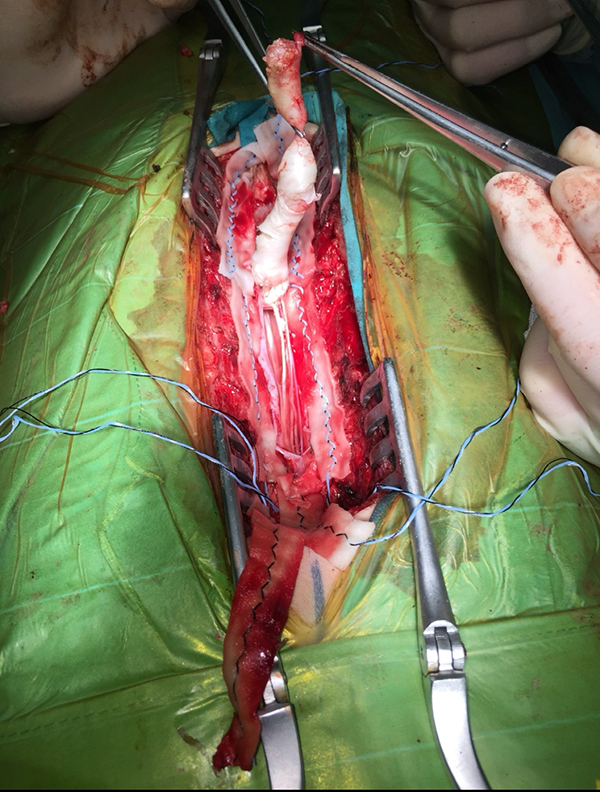

手术中正在从脊髓及神经上分离囊肿。(白色条状物)